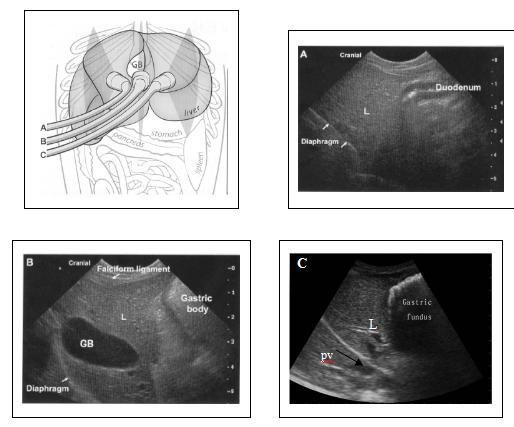

图4-1 正常肝脏的纵断面超声探查通路及声像图。探头从右(A)至左(C)进行扫查,可见胃肠与肝脏位置紧密,镰状韧带位于近场。不同动物的镰状韧带声像图变化较大,通常与动物的肥胖程度有关。肝脏血管(V)横断面表现为圆形的无回声结构。胆囊(GB)位于体中线的右侧。

图4-1 正常肝脏的横断面超声探查通路及声像图。犬仰卧位肋弓下扫查通路。A-C,横断面观,从颅腹侧(A)至尾背侧(C)进行扫查。胆囊位于体中线的右侧。